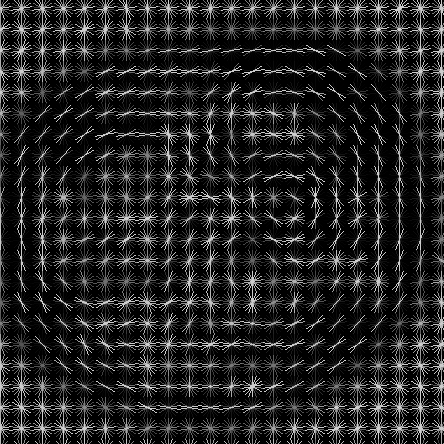

II-A1 Histogram of Oriented Gradients

The first well-known application of HOG was proposed by Dalal and Triggs [9], who used the descriptor for pedestrian detection in still images. This descriptor provides a gridded representation of image gradients, in terms of magnitude and orientation.

In this paper, the Dalal-Triggs variant was applied, using the VLFeat MATLAB implementation [13], with 16x16 blocks and considering 9 orientations, resulting in a 36 bin histogram. An example of the full HOG representation of a MRI scan is shown in Fig. 1(b).